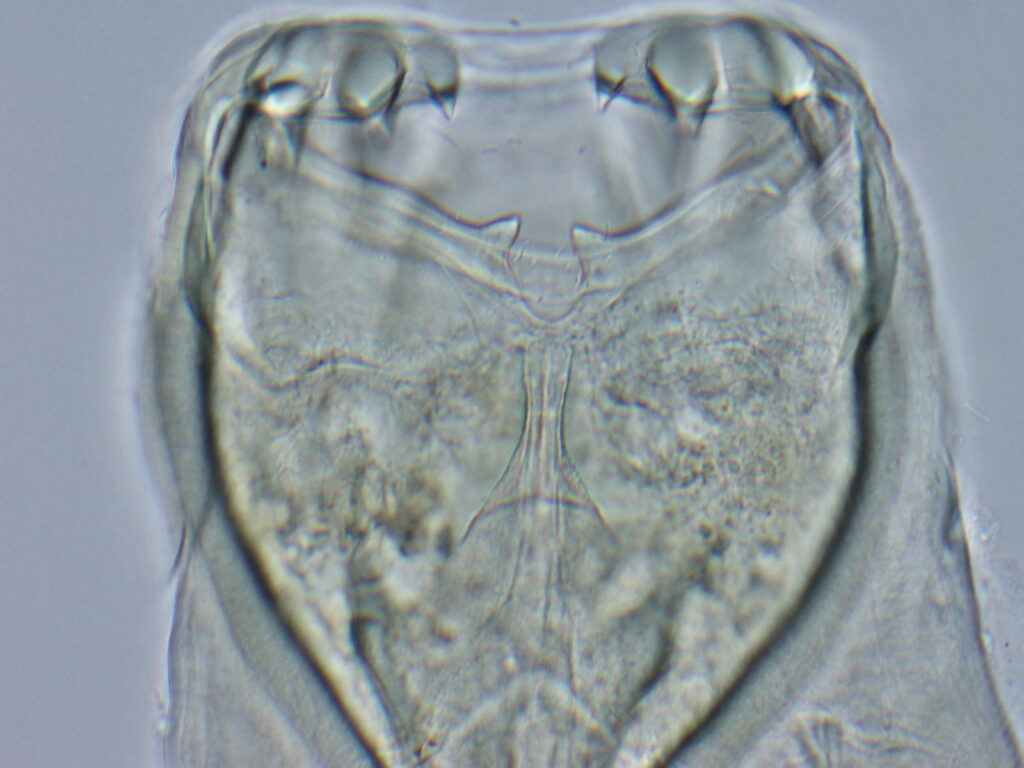

They use their hooklike mouths to latch onto an animal’s intestines, where they feast on tissue fluids and blood. Infected animals can experience dramatic weight loss, bloody stool, anemia and lethargy, among other issues.